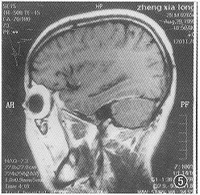

患腦膜炎的X光片針對細菌性腦膜炎,藥物治療中使用氨基糖甙類藥物,或者配合多粘菌素B的治療效果理想。